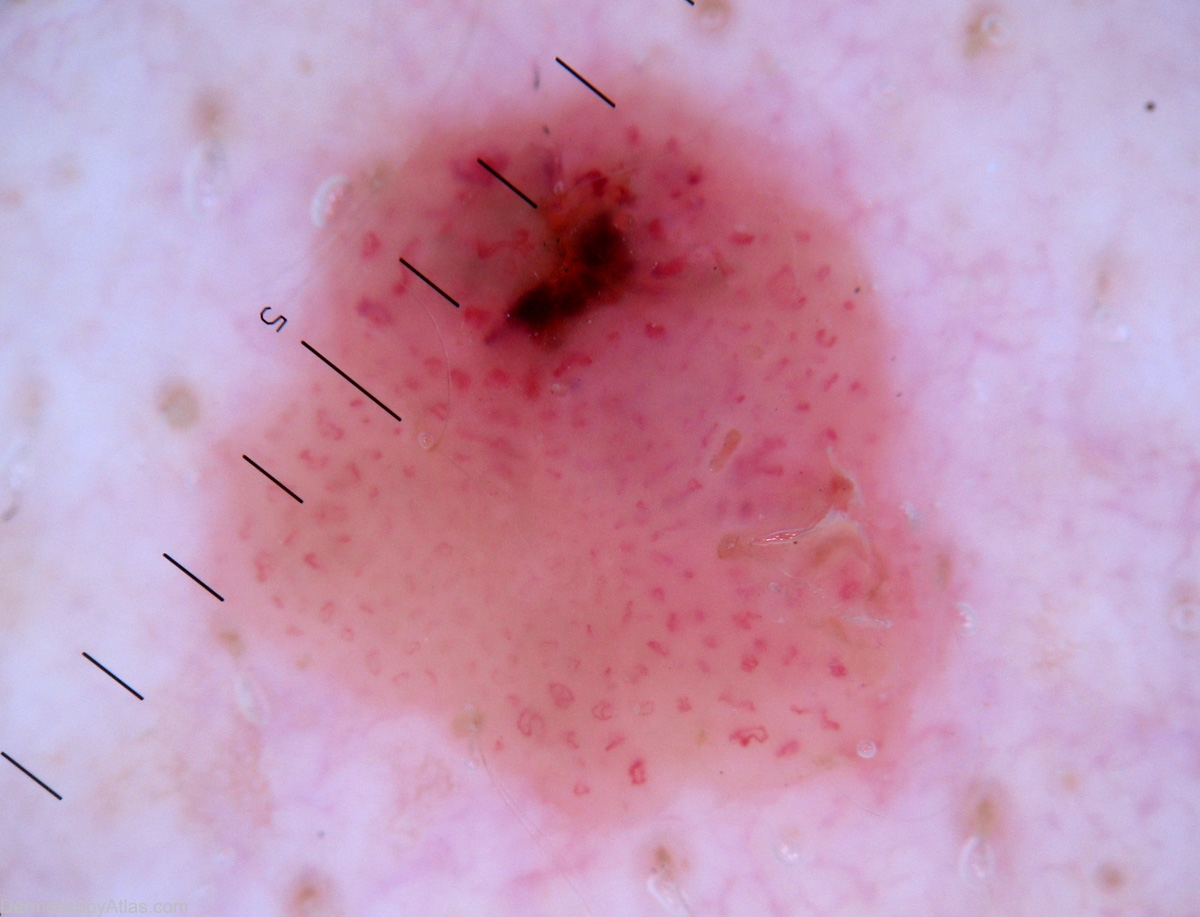

Diagnosis - Seborrhoeic keratosis irritated

Diagnosis: Seborrhoeic keratosis irritated